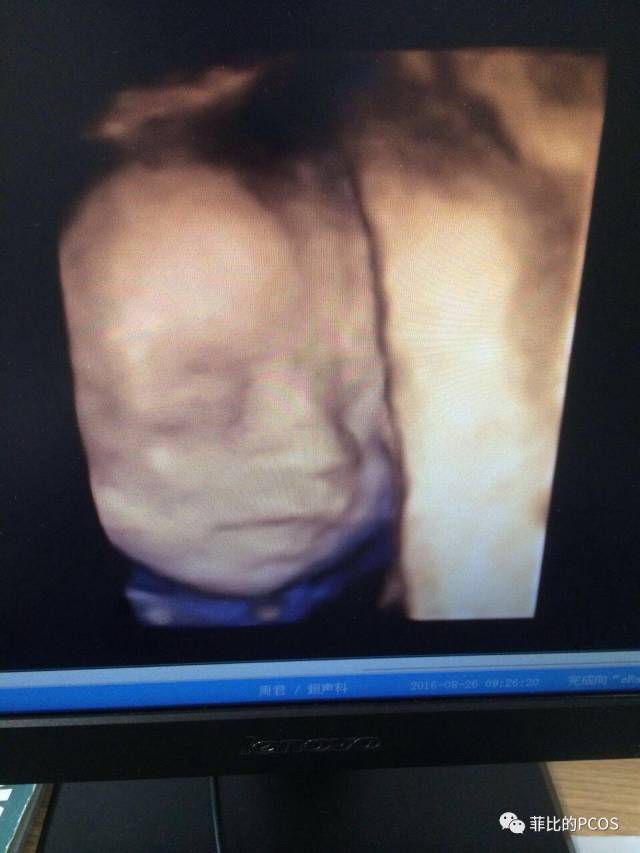

图片

三维时,面部就很清晰了,女宝宝像爸爸。